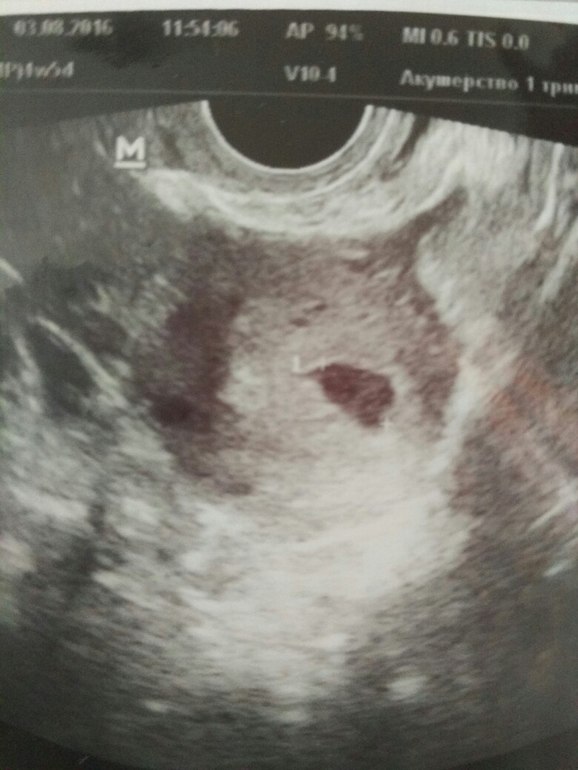

Делала узи на 4 неделе и 5 дней (на 22 дпо), увидели одно ПЯ 11,3 мм, желточный мешочек визуализируется (5 мм)...срок по узи врач поставила 4 недели и 6 дней! Ничего не сказала больше, дала распечатку и сказала приходить через 10-14 дней, чтобы увидеть эмбрион (в анамнезе была ЗБ год назад).

Дома уже посмотрела распечатку фото, меня смутило ПЯ, его форма еще ладно, бывает разная, а вот контуры...кривые и размытые какие-то...испугалась...

Щелково

Главное, что врач при таком размере плодного яйца видит желточный мешок. А насчет размытости контуров - скорее всего, фото сделано в такой момент. В целом четко видно, что есть ободок, это показательный признак. Если у Вас есть сомнения, лучше сдайте кровь на ХГЧ, в динамике, каждые два дня до следующего УЗИ.